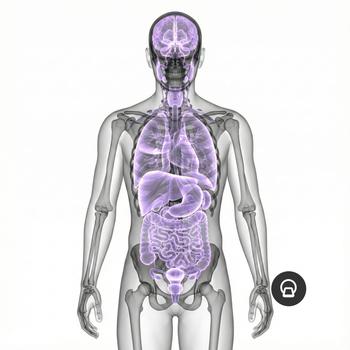

If you have pain in the lower abdomen, irregular bleeding, fertility problems or suspect that something is not right in the lower abdomen, an MRI examination of the pelvis can be the next step to get the right diagnosis. MRI pelvic, also called MRI gynecology, is a painless and radiation-free examination that provides very detailed images of both the uterus, ovaries and fallopian tubes.

The examination is used when other methods such as ultrasound or gynecological examination have not been able to explain your symptoms. With the help of MRI, conditions such as endometriosis, fibroids, cysts, tumors, malformations or effects on nearby organs such as the bladder or intestines can be detected. It is also an important method before fertility treatment or in preparation for surgery.

Whether you are seeking answers to long-term symptoms or following up on previous findings, pelvic MRI gives you and your doctor a clear picture that can form the basis for the right treatment and continued care.